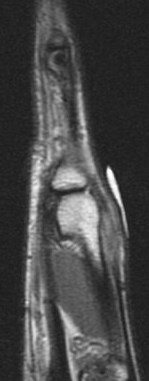

Figure 1 for case Boxers knuckle

Figure 1